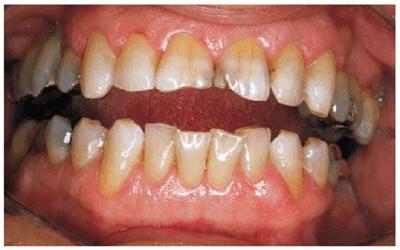

Figures 29-6A, 29-6B, 29-6C, 29-6D, and 29-6E illustrate a patient who did not care much about his

smile. The motivation for pursuing esthetic dentistry was his wife. She thought

that his smile made him look much older than his years. She encouraged him to

have esthetic dentistry by telling him that she would not kiss him until he had

his smile improved. Figures 29-6A, and 29-6D show the worn and discolored central incisors and the

crowded lower anterior incisors. Figure 29-6B shows cosmetic contouring of the lower incisors.

Figures 29-6C, and 29-6E illustrate the completed esthetic improvement following

composite resin bonding of the central incisors.

Figure 29-6A: This 65-year-old man displayed worn, discolored maxillary central incisors with a fractured anterior composite restoration on tooth #9.

Figure 29-6B: Cosmetic contouring of mandibular incisors.

Figure 29-6C: The view after composite resin bonding of his central maxillary incisors.

Figure 29-6D: This man avoided smiling to hide his worn, discolored, and fractured central incisors.

Figure 29-6E: Note how much younger and happier the patient is following his esthetic dental treatment.